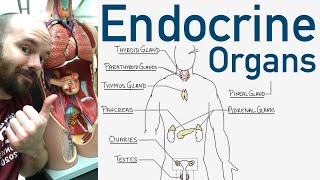

The Endocrine System Endocrine Organs - BEST Way to Learn All the Endocrine Organs and What They Do

Endocrine Organs - BEST Way to Learn All the Endocrine Organs and What They Do Endocrine Glands & Functions | Parathyroidism Nursing | Made Easy NCLEX

The Endocrine System Endocrine Organs - BEST Way to Learn All the Endocrine Organs and What They Do

Endocrine Organs - BEST Way to Learn All the Endocrine Organs and What They Do Endocrine Glands & Functions | Parathyroidism Nursing | Made Easy NCLEX